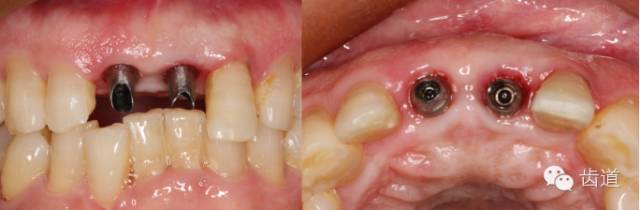

初診照片(正面照)

初診照片(合面照)

植入種植體(唇側(cè)留2-3mm jumping gap)

確定植入深度(齦下3-4mm)

小直徑愈合基臺(tái)就位后唇側(cè)植骨

更換大直徑愈合基臺(tái)